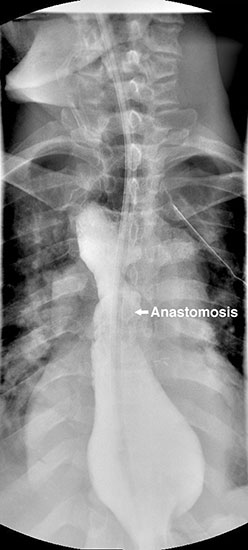

The gastric conduit was advanced into the thoracic cavity and rotated in an organo-axial fashion, such that the fundus was the most cephalad portion of the gastric conduit. With this rotation, the conduit had adequate length to reach the proximal esophagus and was not under tension. A hand-sewn, single-layered anastomosis was then performed between the esophagus and the gastric conduit (Figure 3).

The patient had an uncomplicated course. His nasogastric tube was removed on postoperative day five. A water-soluble esophageal swallow study on postoperative day six demonstrated normal flow of contrast through the anastomosis and stomach into the jejunum, with no evidence of leak or obstruction (Figure 4). The patient was discharged to home on regular diet on postoperative day eleven. Pathologic analysis of the specimen revealed multiple strictures within the esophagus, to a diameter as narrow as 5 mm, and no evidence of malignancy. The patient had complete resolution of his dysphagia on 9 month follow-up and was returning to his baseline weight.

In this clinical scenario, the stomach can still be used as the conduit, but the left gastric artery needs to be maintained to prevent gastric necrosis3. Our case shows that an esophagogastric anastomosis is still possible, but the stomach must be rotated in an organo-axial fashion more excessively than with standard esophagectomy. In our case, the anastomosis was ultimately performed to a more distal position on the gastric conduit than usual, within the fundus. This should not affect gastric emptying substantially but, given this extra rotation, a pyloroplasty should be performed.